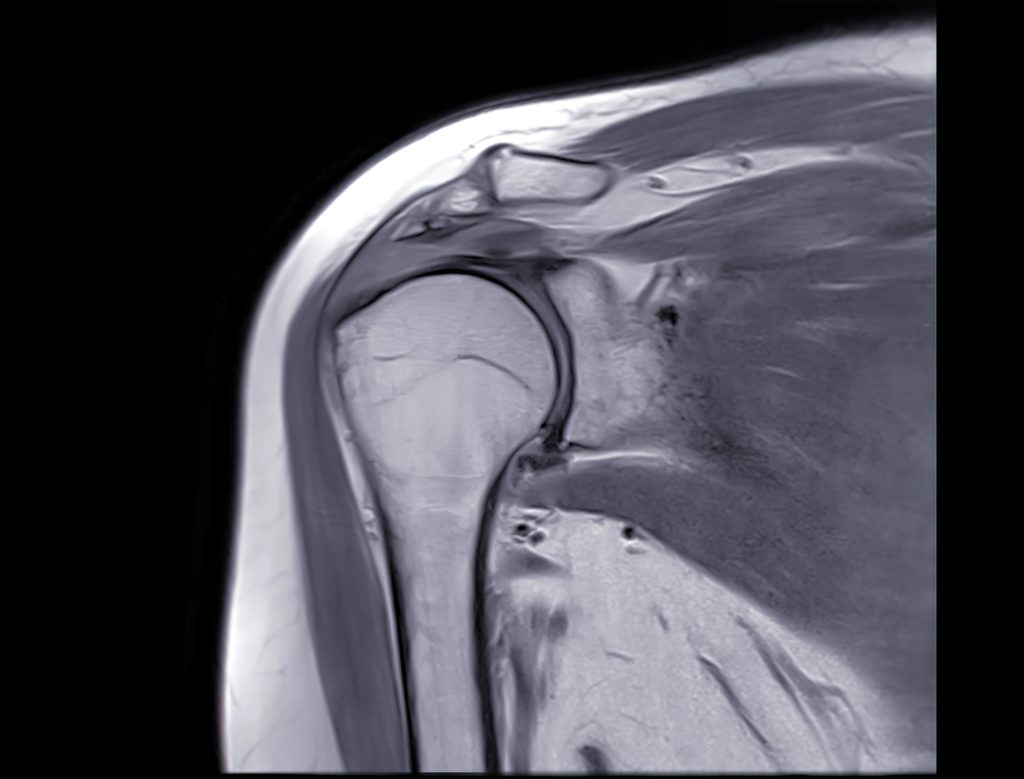

MRI machines are incredibly good at their job. They can detect minute structural changes in soft tissue. They can show a partial-thickness tear that's just a few millimeters. They can reveal tendon fiber disruption that might not affect function at all.

But exquisite sensitivity in detecting structural changes does not equal clinical relevance.

A structural change only matters if it changes how your shoulder functions or causes pain. And this study clearly shows that the vast majority of MRI-detected abnormalities do exactly neither.